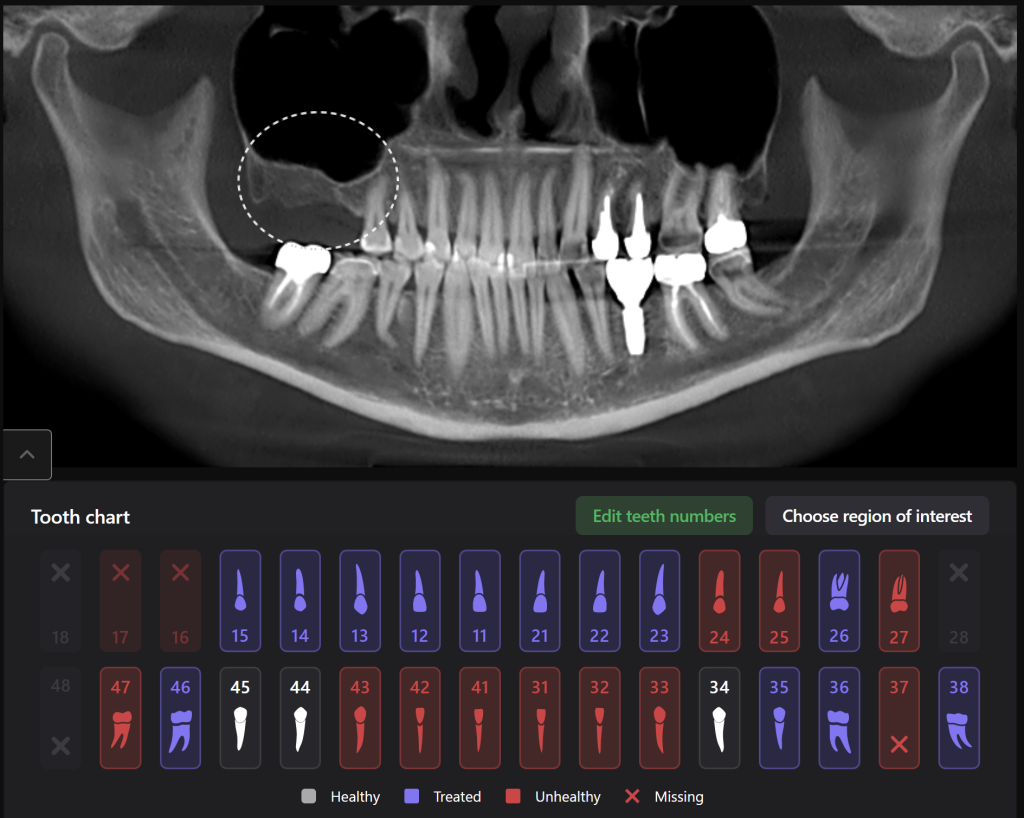

The slide demonstrates the continuation of prosthetic treatment on the lower jaw